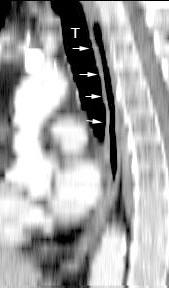

Traqueobroncomegalia de Mounier-Kuhn

Dilatación marcada de tráquea y grandes bronquios.

Traqueobroncomalacia 67% + Protrusión del tejido músculo-membranoso redundante entre los anillos cartilaginosos.(diverticulosis traqueal)

Infección respiratoria recurrente (88%)

Debilidad del aparato muco -ciliar Fumadores.